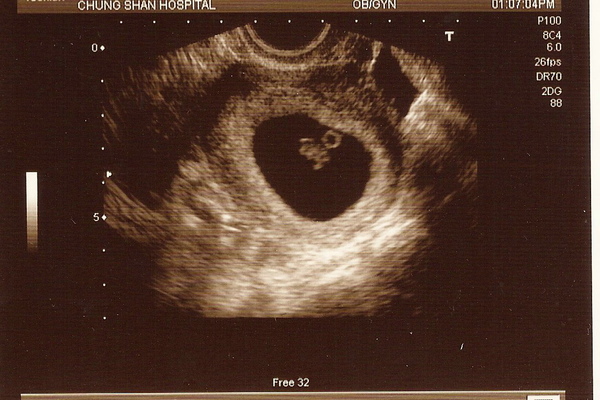

今天是跟小牛初次見面的日子。之前寶寶都還太小,即使照超音波也看不出甚麼。今天主要要去檢查是否有子宮外孕的情況,還有最重要的,要聽聽小牛的心跳囉。

小鳥爸比跟小牛的外婆,陪著兔子媽咪一起進入診間。因為小牛還很小,用腹部超音波無法照得清楚,所以只能照陰部超音波。一開始兔子有點緊張,不知道會不會痛,也不知道整個程序開如何進行。還好羅醫師很有經驗,一點也不痛。

羅醫師很熟練的拿著儀器操作~ 轉個幾下....哇哇哇! 我看見寶寶啦!